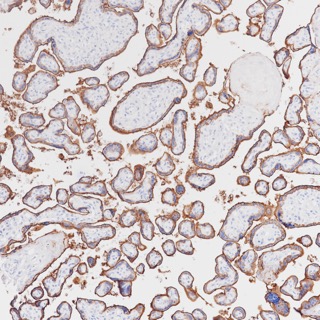

• Immunohistochemistry of paraffin-embedded human placenta using PLAP antibody at dilution of 1:200 (200x lens).